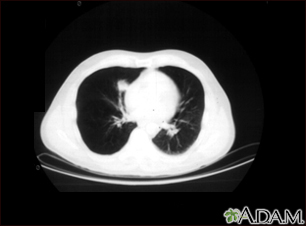

BACK TOTOP Browse A-ZSearchBrowse A-ZABCDEFGHIJKLMNOPQRSTUVWXYZ0-9 Lung nodule, right lower lung - CT scanBackLung nodule, right lower lung - CT scanA CT scan showing a mass in right lower chest near the heart (left side of photograph). E-mail FormEmail ResultsName:Email address:Recipients Name:Recipients address:Message: Review Date: 8/19/2024 Reviewed By: Allen J. Blaivas, DO, Division of Pulmonary, Critical Care, and Sleep Medicine, VA New Jersey Health Care System, Clinical Assistant Professor, Rutgers New Jersey Medical School, East Orange, NJ. Review provided by VeriMed Healthcare Network. Also reviewed by David C. Dugdale, MD, Medical Director, Brenda Conaway, Editorial Director, and the A.D.A.M. Editorial team. The information provided herein should not be used during any medical emergency or for the diagnosis or treatment of any medical condition. A licensed medical professional should be consulted for diagnosis and treatment of any and all medical conditions. Links to other sites are provided for information only -- they do not constitute endorsements of those other sites. No warranty of any kind, either expressed or implied, is made as to the accuracy, reliability, timeliness, or correctness of any translations made by a third-party service of the information provided herein into any other language. © 1997- A.D.A.M., a business unit of Ebix, Inc. Any duplication or distribution of the information contained herein is strictly prohibited. © 1997- All rights reserved. A.D.A.M. content is best viewed in IE9 or above, Firefox and Google Chrome browser.Content is best viewed in IE9 or above, Firefox and Google Chrome browser.

Lung nodule, right lower lung - CT scanBackLung nodule, right lower lung - CT scanA CT scan showing a mass in right lower chest near the heart (left side of photograph). E-mail FormEmail ResultsName:Email address:Recipients Name:Recipients address:Message: